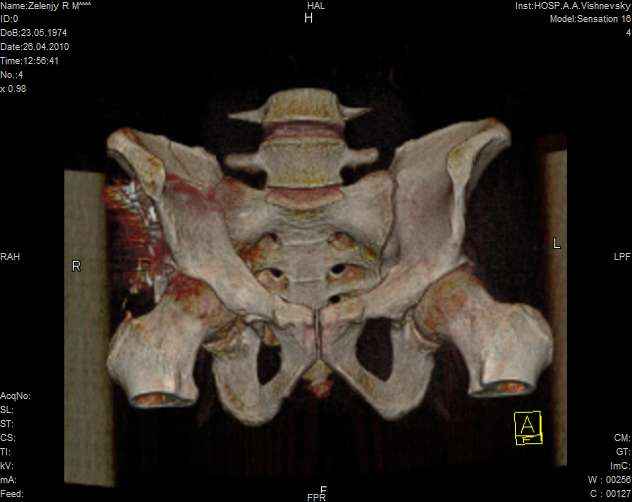

к таковым себя не причисляю, но...обычное дело для нашей страны - выкладывать 3D и не показывать стандартные проекции Judet. Дигност представляет те ракурсы, которые по-его мнению наиболее информативны, более того комп сам достраивает какие-то мелкие повреждения по 3D по своему усмотрению. По данной реконструкции можно предполагать высокий двухколонный перелом с оскольчатыми передней и задней колоннами, оскольчатую высокую переднюю колонну с задним полупоперечником или одно из перечисленных с вовлечение КПС. У меня впечатление за второй вариант, но нужно обследовать нормально - проекции, сканы.

Когда перелом не получается отнести к какому либо типу - эффективнее всего описать более детально. В дальнейшем проще бывает сортировать, и что важнее - "руководство к действию" бывает более обоснованным. В данном случае графа клинического диагноза может выглядеть так: Застарелый разрыв правого крестцово-подвздошного сочленения, консолидирующиеся со смещением переломы крыла и тела правой подвздошной кости, обеих колонн и задней гемисферы правой вертлужной впадины. Состояние после остеосинтеза.

>Застарелый разрыв правого крестцово-подвздошного сочленения, консолидирующиеся со смещением переломы крыла и тела правой подвздошной кости, обеих колонн и задней гемисферы правой вертлужной впадины. Состояние после остеосинтеза.

Судя по представленным реконструкциям (не очень хорошего качества - много наводок)

мы имеем дело с полупоперечным переломом у которого отломался задний край или его отломали, превратив перелом в полный двухколонный.

По отдельным срезам и тем более по реконструкции трудно судить о сращении крыла и задней колонны с осевым скелетом.

Из того минимума, что представлено, мне кажется, мы имеем дело с двухколонным переломом вертлужной впадины. Обычно медиальный (центральный) "вывих" головки встречаются в сложных двухколонных переломах со смещением.